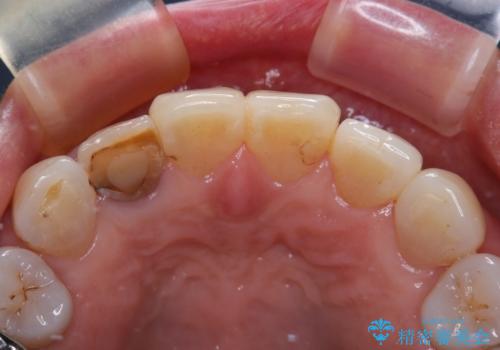

- 奥歯の目立つ銀歯と、神経が失活して変色した前歯を気にして来院された患者様です。

銀歯と歯の間に隙間があり、冷たいものがしみる知覚過敏の症状が認められたため、銀歯を白くするだけでなく、知覚過敏症状の改善も狙って補綴治療を行うこととしました。